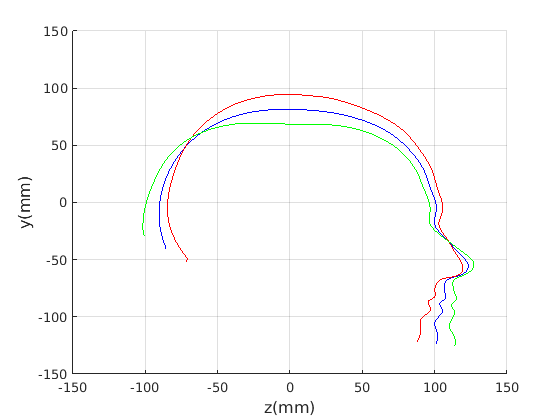

Figure 17 shows all 100 profiles overlaid with the same alignment scheme. The median value of major ellipse axis and the ellipse centre-nasion angle differ by 3.6 degrees, so that when the nasion angle is fixed at -10 degrees, the median ellipse angle is -6.4 degrees (cf. -7.4 degrees with manual landmarking of the nasion). We noted regularity in the orientation of the fitted ellipse as is indicated by the clustering of the major (red) and minor (green) axes in Fig. 17 and the histogram of ellipse orientations in Fig. 18. For most people, the major axis of the ellipse is closely aligned with the y-axis (upright), and titled slightly forwards. A minority of heads (9%) in the training sample have their major ellipse axes closer to the vertical (these relatively tall and short heads are known as brachycephalic.) Ellipse axis clustering (relative to the fixed ellipse centre-nasion line) does not appear to be sharply defined. This is because many crania are close to circular in cross-section, making the orientation of these angles sensitive to small changes in shape from one person to the next. Note also the variation at the back of the head due to a variety of hair styles, some of which protrude from under the cap. We limit the region over which we model the cranial shape in order to crop this unwanted data out.

To provide a comparsion with ECN, the form/shape variation modes extracted from a GPA-based alignment are given in Fig. 21 for full head and Fig. 21 for cranium only.

|

|

|

|

|

|

|

|

|

|

|

|

|

|

|

|